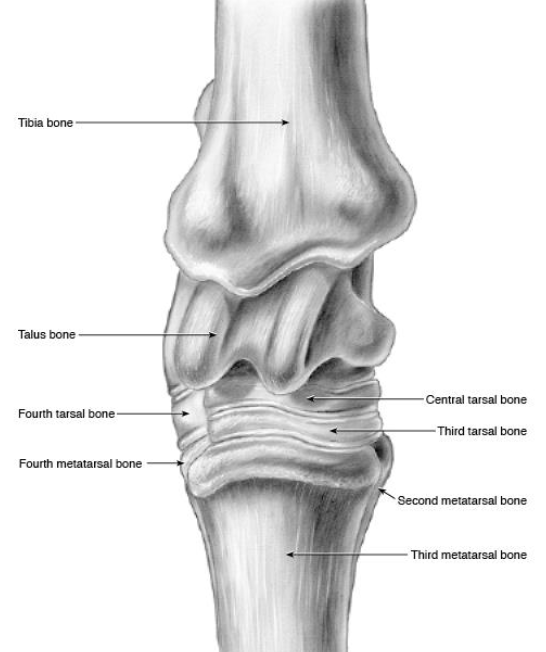

what are the bones of the tarsus

distal tibia, calcaneus + sustentaculum tali (fused), talus (+ medial and lateral trochlea), central tarsal bone, 3rd tarsal bone, 4th tarsal bone, fused 1 & 2 tarsal bone, proximal 2 3 and 4 metatarsal bones